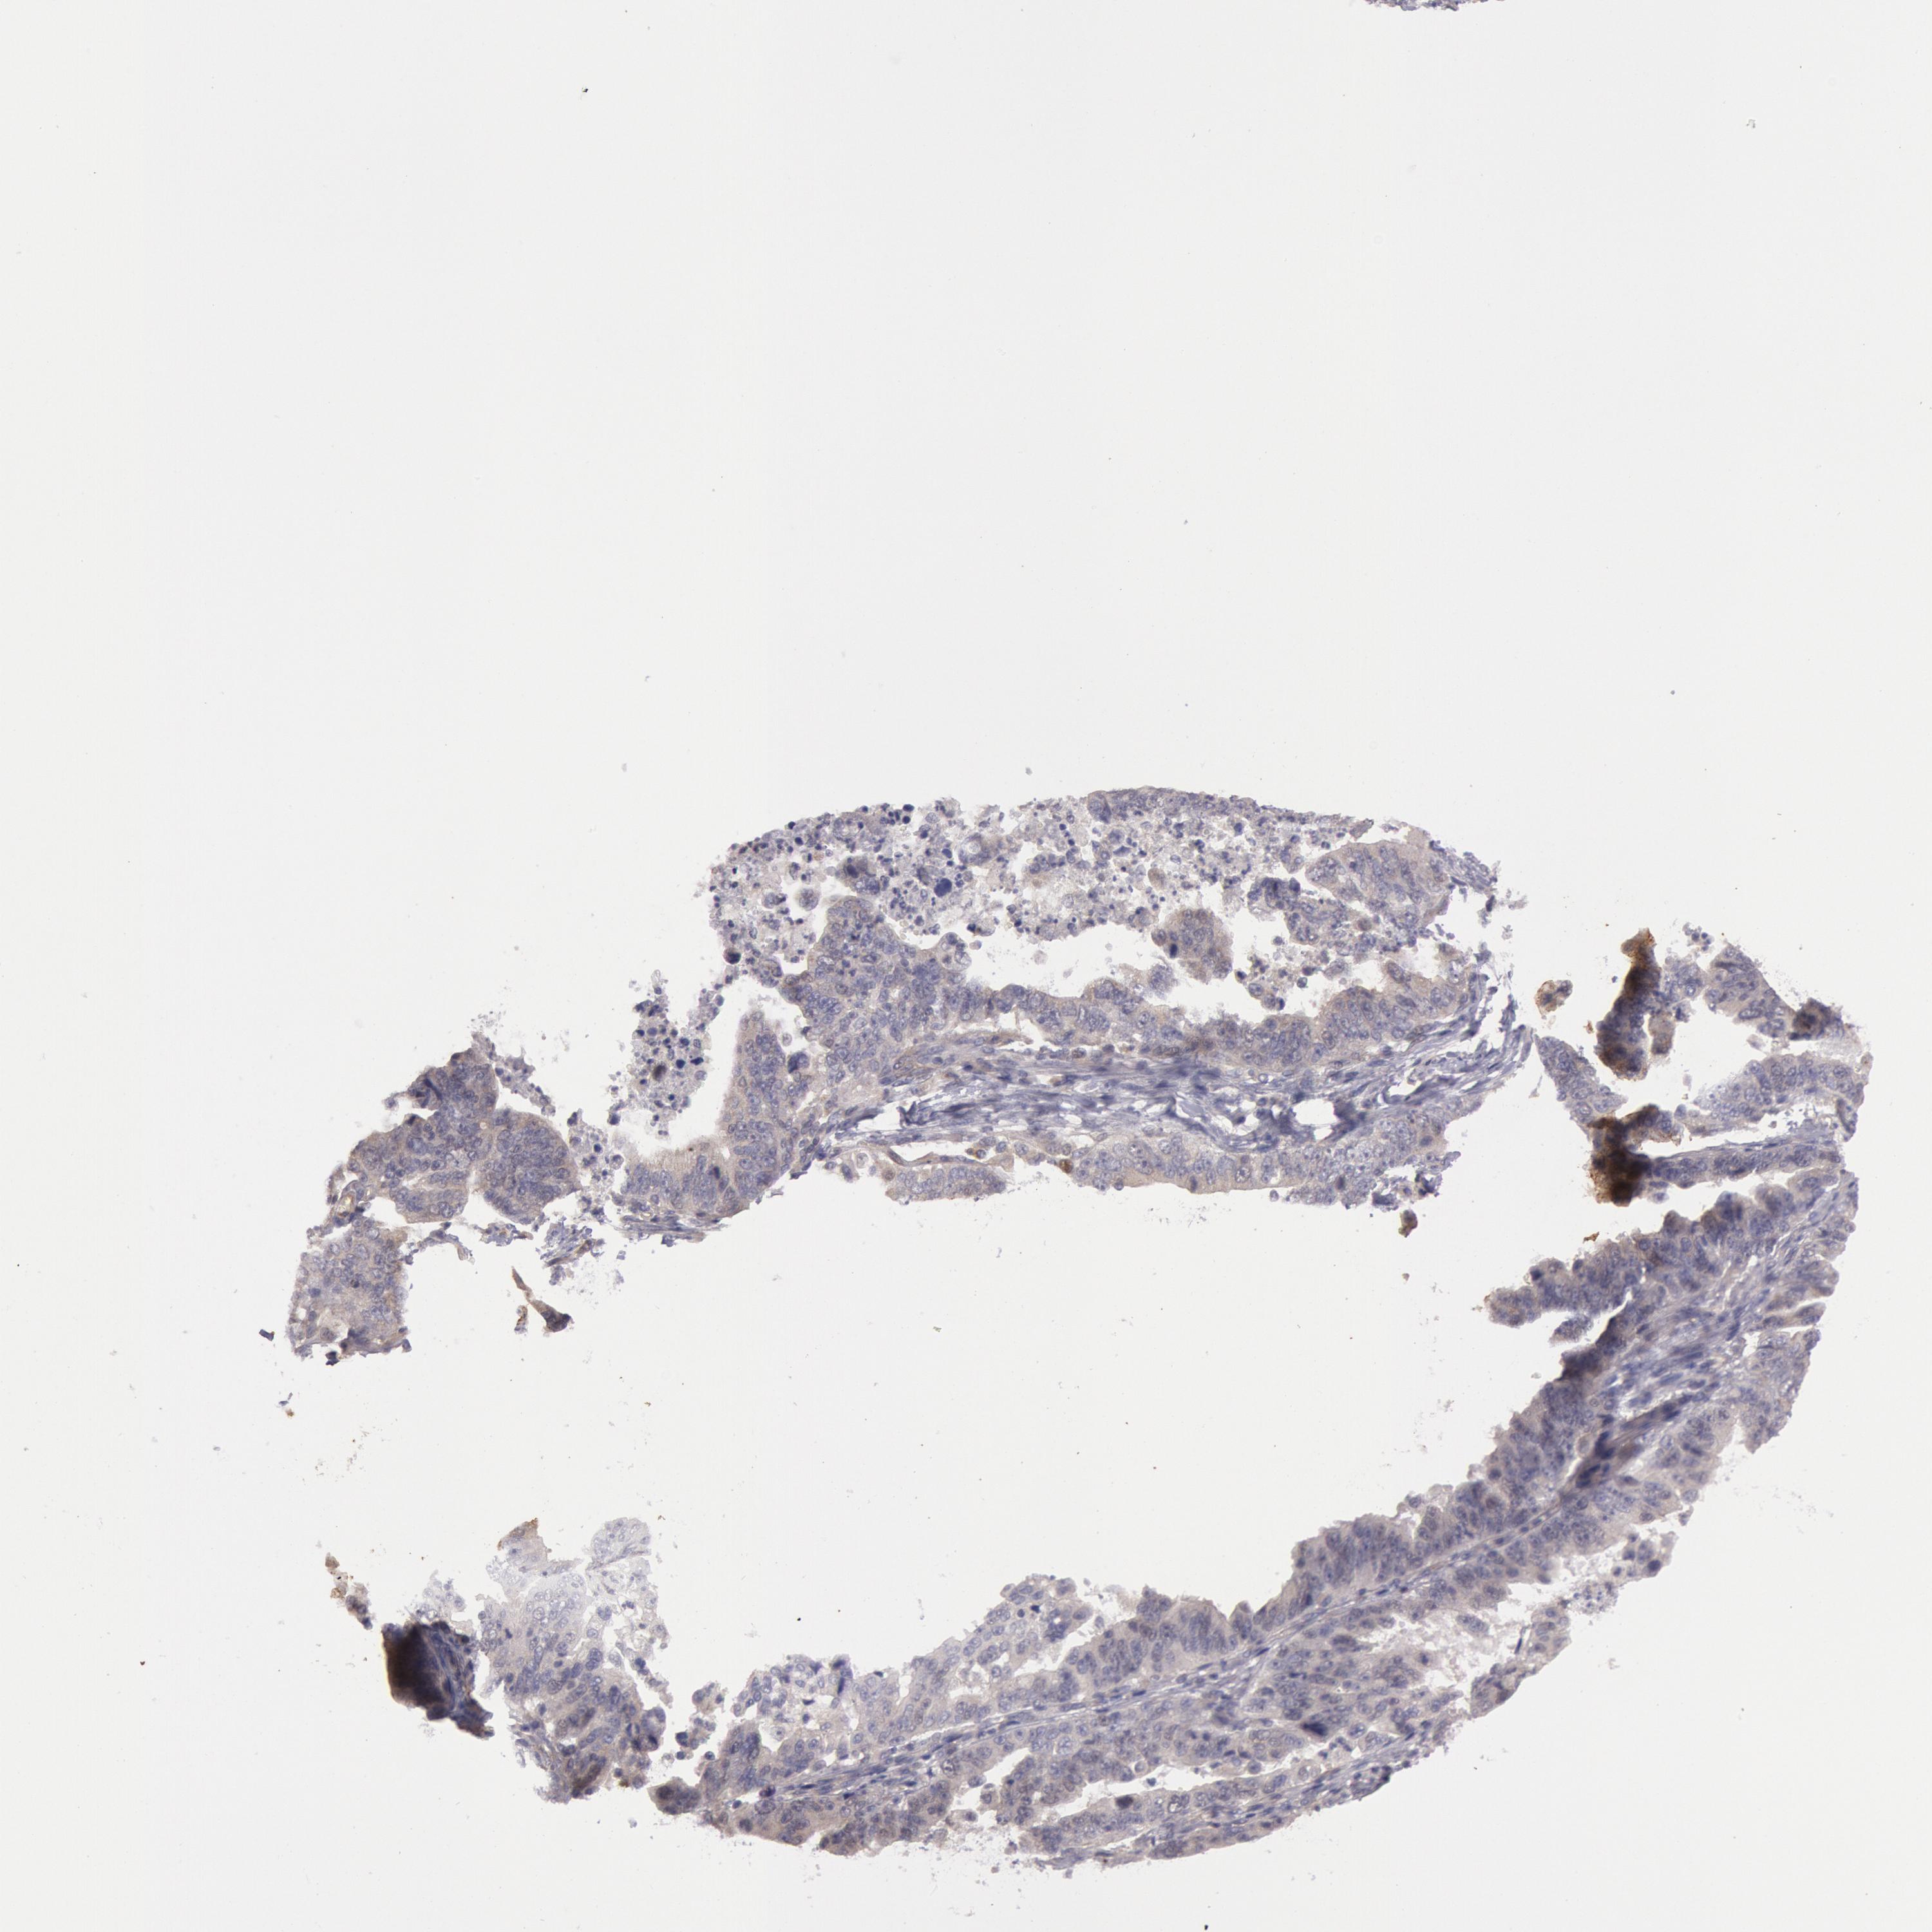

STOMACH CANCER - Protein expressioni

A mouse-over function shows sample information and annotation data. Click on an image to view it in a full screen mode. Samples can be filtered based on level of antibody staining by selecting one or several of the following categories: high, medium, low and not detected. The assay and annotation is described here.

Note that samples used for immunohistochemistry by the Human Protein Atlas do not correspond to samples in the TCGA dataset.

Antibody stainingi

Antibody staining in the annotated cell types in the current human tissue is reported as not detected, low, medium, or high, based on conventional immunohistochemistry profiling in selected tissues. This score is based on the combination of the staining intensity and fraction of stained cells.

Each image is clickable and will lead to virtual microscopy that enables deeper exploration of all samples and also displays staining intensity scores, fraction scores and subcellular localization as well as patient and tissue information for each sample.

Antibody HPA001196

Staining

High

Medium

Low

Not detected

Intensity

Strong

Moderate

Weak

Negative

Quantity

>75%

75%-25%

<25%

None

Location

Nuclear

Cytoplasmic/membranous

Cytoplasmic/membranous,nuclear

Adenocarcinoma, NOS